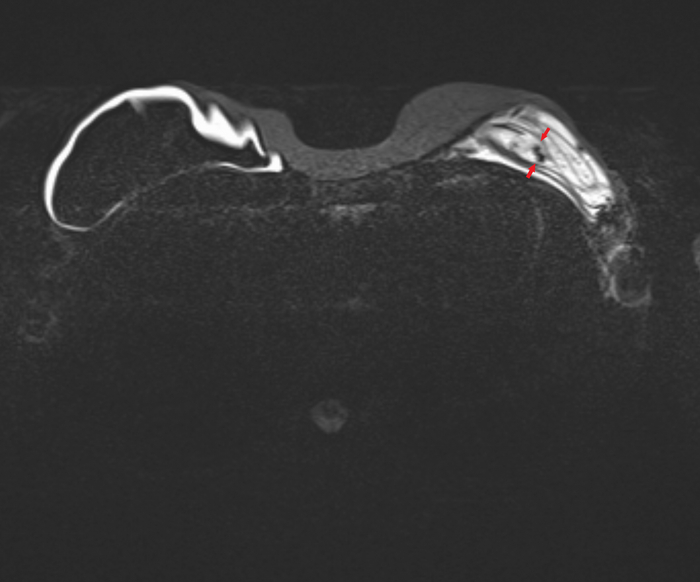

Пациентка, 64 года, перенесла двустороннюю мастэктомию (удаление обеих молочных желёз) по поводу рака 14 лет назад с пластикой с обеих сторон двухкамерные имплантами. Сейчас клинически подозревают фиброз капсулы и возможно разрыв левого импланта. Для подтверждения диагноза провели МРТ молочных желёз (только нативную часть протокола, т.е. без в/в введения контрастного вещества, от которого пациентка отказалась).

Начнём с краткого обзора здорового импланта:

Т2-взвешенное изображение

где центрально расположена камера, заполненная физ.раствором (голубой цвет), на периферии - камера, заполненная силиконом (красный цвет), и отграничено это всё фиброзной капсулой, которой тело старается отграничить инородный объект (пунктирная линия):

если мы сравним правый имплант с левым, то разница очевидна, тут не надо быть рентгенологом, чтобы понять что что-то тут не то, а именно сам имплант меньше, интенсивность сигнала иная (цвет более тёмный) + видны какие-то линии внутри импланта (красные стрелочки):

Линии эти - так называемый признак "лингвини" (или по-английски linguine sign), т.к. похожи они на одноимённую итальянскую пасту лингвини:

и являются ни чем иным как спавшимися стенками камер имплантов, что указывает на внутрикапсульный (в пределах образовашейся фиброзной капсулы) разрыв импланта, но без свободного выхода содержимого в окружающие мягкие ткани.

Интенсивность сигнала поменялась из-за того, что физ.раствор частично смешался с силиконом, и вследствие этого определяются пузырьки физ.раствора в силиконе - т.н. признак "салатного масла" или "salad oil sign" (капли, как при добавлении масла в воду):

которые я отметил красными стрелочками:

и на секвенции с подавлением воды, которая становится на картинке "чёрной" (синяя звёздочка), а силикон остаётся "белым" (красная звёздочка):

Имплант, соответственно, больше не жизнеспособен и его следует заменить.